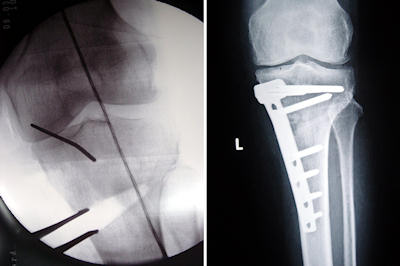

Proksimal tibial osteotomi, kapalı kama, açık kama, dome (kubbe) ostetomisi veya hemikalotazis teknikleri ile yapılabilir.Kapalı kama osteotomisi

Lateral tibial metafizden kama çıkartılarak yapılan osteotomidir. (Resim 2) Geçmiş yıllarda en yaygın uygulanan bu osteotominin en önemli avantajları teknik olarak kolay olması, ve medial korteks kırılmadığı sürece stabil bir osteotomi olmasıdır. Buna karşın, proksimal tibial metafizde kemik kaybına yol açması, fibuler osteotomi gerektirmesi ve en fazla 15 derece düzeltmeye izin vermesi tekniğin dezavantajlarıdır. Sagital planda tibial “slope” azalmasına yol açar. Daha sonra total diz artroplasitisi gerektiğinde en fazla sorun yaratacak olan osteotomi şeklidir. Osteotomi sırasında medial kortikal fissür oluşursa düzeltme kaybı veya translasyon riski vardır (Pape D: Orthopade 2004, 33(2):208-17.)

Medial tibial metafizden yapılan inkomplet açık kama osteotomisidir (Resim 4). Küçük cerrahi kesi ile yapılabilir. Fibuler osteotomi gerekli değildir. Proksimal metafizde kemik kaybına yol açmaz. Kamanın yeri değiştirilerek tibial eğim artırılıp azaltılabilir. Bu özellike çapraz bağ laksitesi olan olgularda avantajlıdır. Buna karşın 7-10 mm’den fazla düzeltmelerde greft gerekli olabilir. Bunun için iliak kanat, allogreftler veya sentetik kemik dolgularının kullanımı rapor edilmiştir (Koshino T: Biomaterials 2001; Hernigou P: Knee, 2001; Levai JP: Rev Chir Orthop Reparatrice Appar Mot. 2003). Osteotomi sonrası çeşitli serilerde 2-8 derece arası tibal eğim artışı rapor edilmiştir(Marti R: Arthroscopy 2004, 20(4):366-72). Ayrıca eklem çizgisi yükselmesine bağlı patella infera görülebilir. Son zamanlarda, bu osteotomi yapıldığında, iç yan bağ lifleri sub periostal gevşetilmediği takdirde medial kompartmanda basınç artışı olabileceği konusunda endişeler ortaya çıkmıştır..

Kapalı kama osteotomisinde kullanılır. Stabilite için karşı korteksin sağlam olması gerekir. Kendisi yeteri kadar güçlü olmadığı için 2-3 hafta eksternal destek ve immobilizasyon gerektirir, buna rağmen düzeltme kaybı olabilir ve bazı hastalarda cilt altında rahatsızlığa yol açtığı için çıkartılması gerekebilir.T-L plaklar veya kamalı plak ile tespit

Stabil tespit sağlar ve erken harekete izin verir. Düzeltme kaybı yoktur. Daha geniş yaklaşım ve disseksiyon gereklidir. Artroplasti öncesi veya sırasında çıkartılması gerekir. Kamalı kama ve kubbe osteotomileri için kullanılır.Açık kama plakları

Osteotomi sonrasında, fragmanları ayrı tutacak diş ya da bloklara sahip özel tasarlanmış plaklardır. Minimal disseksiyon ile yerleştirilirler, 7 mm altında distraksiyon için greft ihtiyacı yoktur ancak lateral korteks kırılırsa stabilite sorunları ortaya çıkabilir.Tomofix

Açık kama plakları ile korreksiyon kayıplarının sık olması nedeniyle, AO grubu tarafından bu bölge için özel olarak geliştirilmiş, daha büyük ve rijid tespit sağlayan bir implanttır (Lobenhoffer P :KSSTA, 2003 11(3):132-8 ). Vidaların plağa kilitlendiği LCP esaslarına uygundur. Tuberositas tibia, distal fragmanda kalacak şekilde bi-planar bir osteotomi gerektirir. Erken harekete izin verir, plağı distal vidaları perkutan yerleştirilebilir, pes anserinusu korumak için özel “spacer” lar üzerine yerleştirilir.